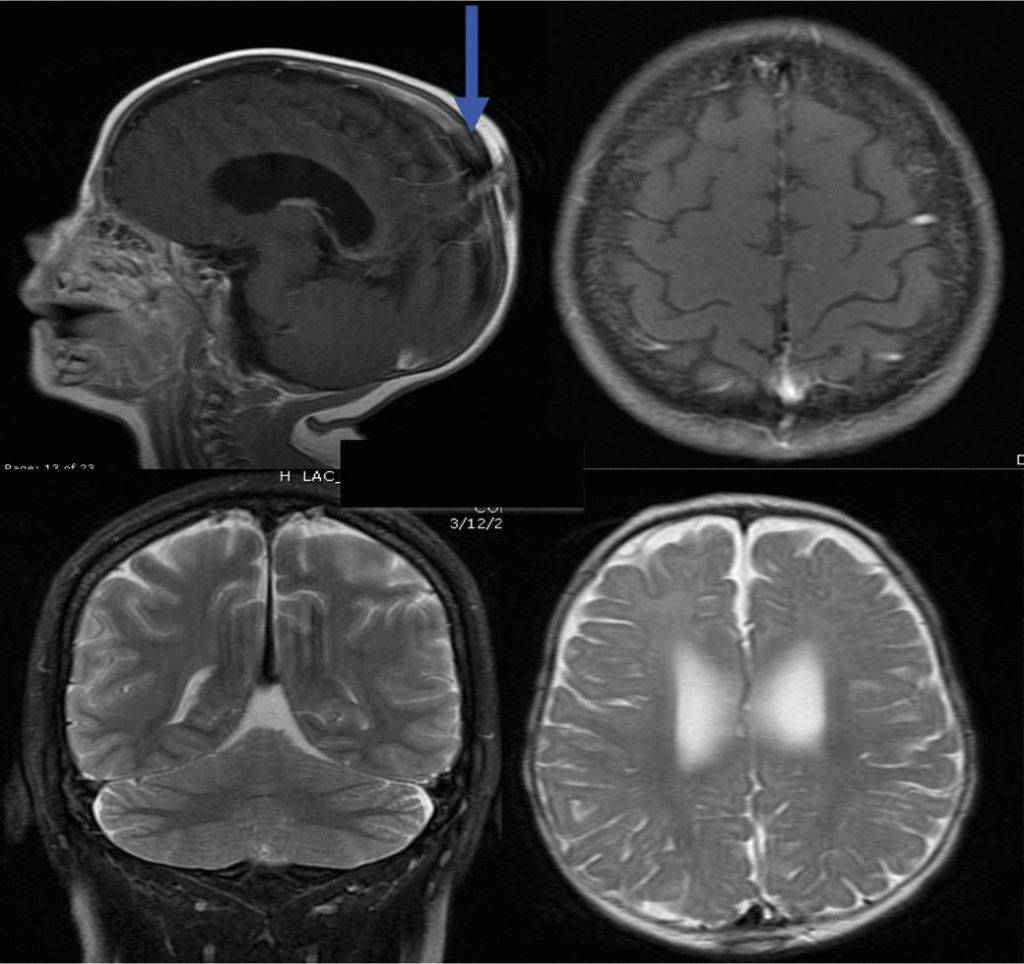

- МРТ головного мозга. МРТ-исследование головного мозга отличается высокой чувствительностью и позволяет визуализировать оба полушария мозга, его стволовую часть, желудочковую систему и другие структуры. С помощью МРТ головного мозга могут быть вывялены сосудистые аномалии, расширение сосудов, кровоизлияния, опухоли, очаги воспаления и дегенерации, скопления жидкости и т.д.

Что показывает МРТ головного мозга

Получив 3D-изображения головного мозга в разных проекциях, врач имеет возможность рассмотреть в деталях каждую его область. Это позволяет сделать выводы о:

-

процессах, протекающих в тканях головного мозга;

состоянии кровеносных сосудов;

наличии, расположении, формах и размерах новообразований, гематом или тромбов;

наличии, стадии и локализации других патологий головного мозга.

Если результаты оказались недостаточно точными или требуется дополнительная визуализация определенного участка, может быть назначена МРТ головного мозга с контрастированием. Введение контрастирующего препарата позволяет получить более точное представление о строении ткани мозга или патологического образования, уточнить его границы.